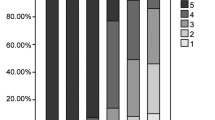

The subjective PET image quality was independently rated on a 5-point Likert scale by 3 nuclear radiologists (a senior radiologist with > 8-year experience, a radiologist > 5-year experience, and a junior radiologist with 1 year of post-fellowship experience reading PET/CT scans) blinded to patient history and dose group of the images. Four simulated dosing levels were included in the qualitative PET assessments (Fig. 1): 1.85 MBq/kg (1/2-dose, G300s), 0.37 MBq/kg (1/10-dose, G60s), 0.25 MBq/kg (1/15-dose, G40s), and 0.12 MBq/kg (1/30-dose, G20s). A 5-point Likert scale was used for (1) overall impression of the image quality, (2) conspicuity of the major suspected malignant lesions, and (3) image noise. The 5-point Likert scale for overall image quality comprises five categories which are defined as score (1) state-of-the-art quality, (2) superior to the regular image quality of daily practice. (3) equal to the regular quality of daily practice, (4) barely diagnostic, and (5) non-diagnostic (Supplementary Table 1). Among which, grade 3 indicates a quality of clinical routine image quality by a digital PET/CT scanner (FOV, 22.1 cm; acquisition time, 1.5–2.0 min/bed positions, 6–10 bed position/patient). Example images of grades 5–1 (5: excellent, 1: poor) have been illustrated in Fig. 1.

Image quality

For the subjective study, the inter-rater agreements of Likert scoring were substantial for the overall image quality, lesion conspicuity, and image noise, with Fleiss kappa values of 0.769, 0.844, and 0.906, respectively. The subjective image quality scores were compared between G300 s, G60s, G40s, and G20s, where Table 2 listed the mean value ± SD of Likert scoring. G300 s showed an excellent image quality with a grade of 5, for which all perspectives were scored in a range of 4–5. Overall image quality was 4.2 ± 0.4 for G60s, 3.4 ± 0.5 for G40s, and 2.2 ± 0.4 for G20s. Image noise of G60s, G40s, and G20s were scored 3.8 ± 0.4, 3.0 ± 0.3, and 2.0 ± 0.5, respectively. For lesion conspicuity, it illustrated a similar variation tendency compared with image quality and noise (G60s, 4.0 ± 0.4; G40s, 3.7 ± 0.5; G20s, 2.7 ± 0.5). Between any two groups in reconstructed subsets (G300 s, G60s, G40s, and G20s), the scores of overall image quality, lesion conspicuity, and image noise were significantly different (p < 0.001 with/without Bonferroni correction), except for lesion conspicuity between G40s and G60s (p < 0.037 with Bonferroni correction).